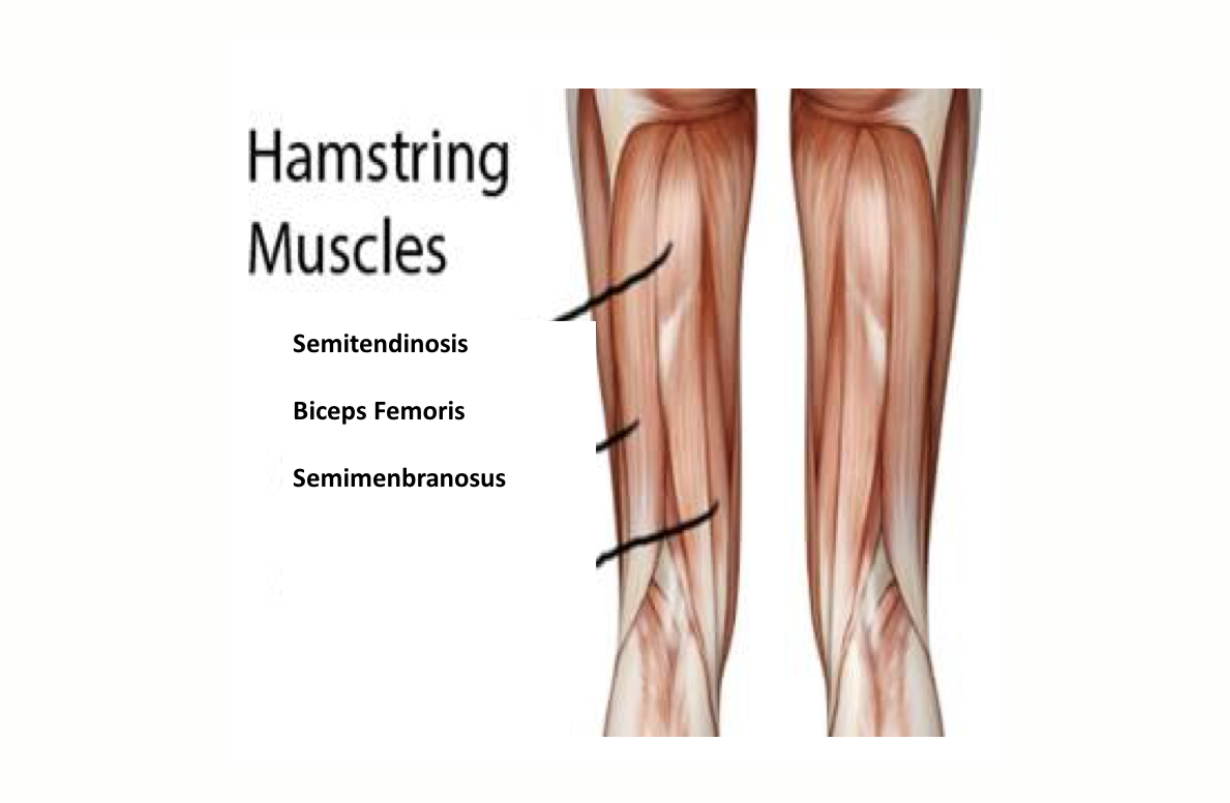

Torn Hamstring

Partial or complete rupture of the semimembranosis, semitendinosis and/or the biceps femoris muscles. BENEFICIAL POSES: Supta Virasana, Ustrasana, Utkatasana, Purvottanasana, (see picture) EXPLANATION: The hamstrings extend the hips and flex the knee. Poses that replace the hamstrings' function at these joints will strengthen alternative muscles and relieve some of the strain on the healing hamstrings. REFEENCE:Rachiwong S1, Panasiriwong P, Saosomphop J, Widjaja W, Ajjimaporn A.Effects of Modified Hatha Yoga in Industrial Rehabilitation on Physical Fitness and Stress of Injured Workers. J Occup Rehabil. 2015 Sep;25(3):669-74. doi: 10.1007/s10926-015-9574-5.